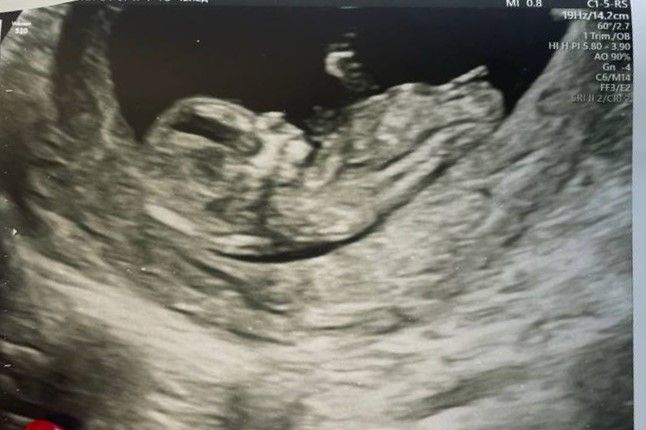

Девочка или мальчик? Пол по половому бугорку))

По половому бугорку я бы предположила девочку 🌷